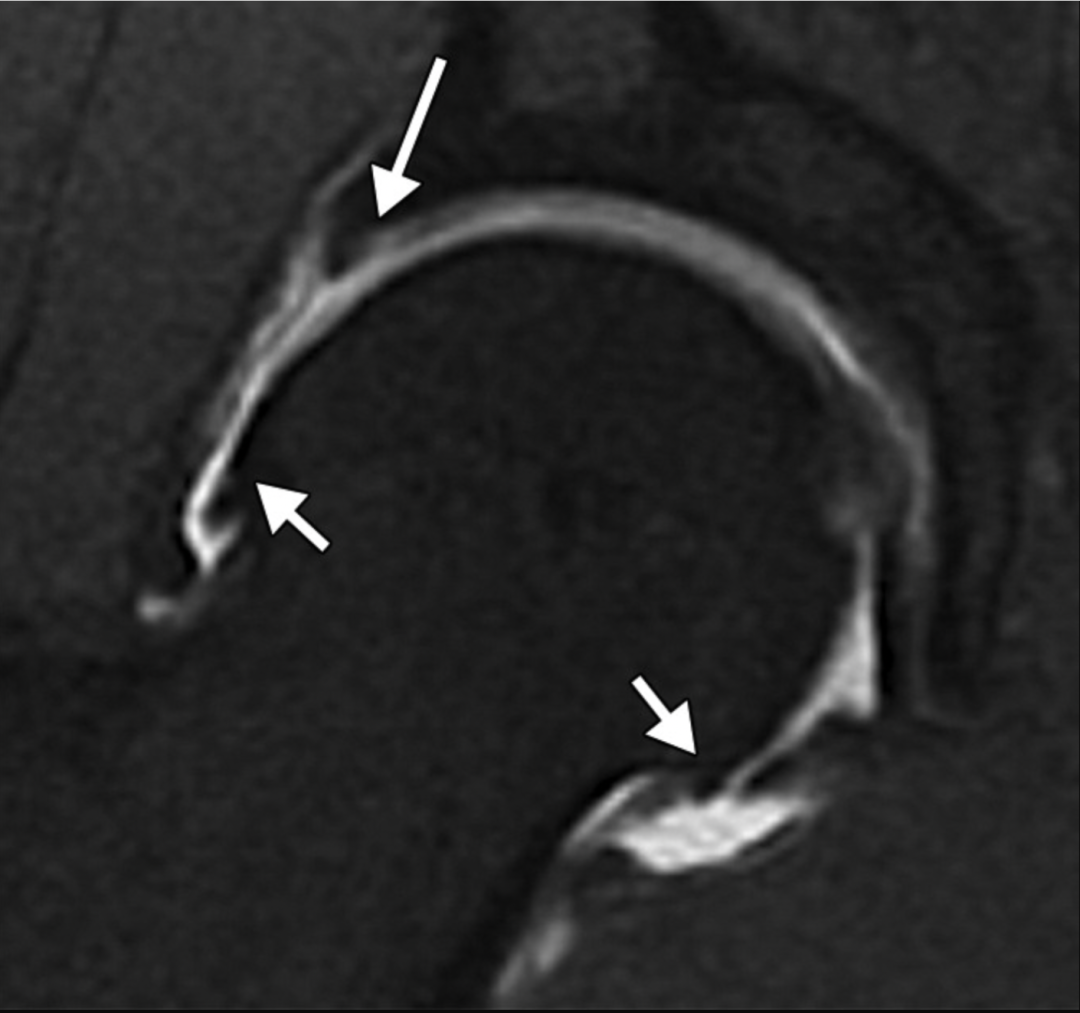

55岁FAI男性,软骨脱层:3T磁共振矢状位中间加权脂肪饱和快速自旋回波(FSE)图像显示,髋臼处软骨异常,软骨下骨区域出现高信号强度,且该区域表面覆盖有一层较暗的低信号软骨(箭头所示)。[7]